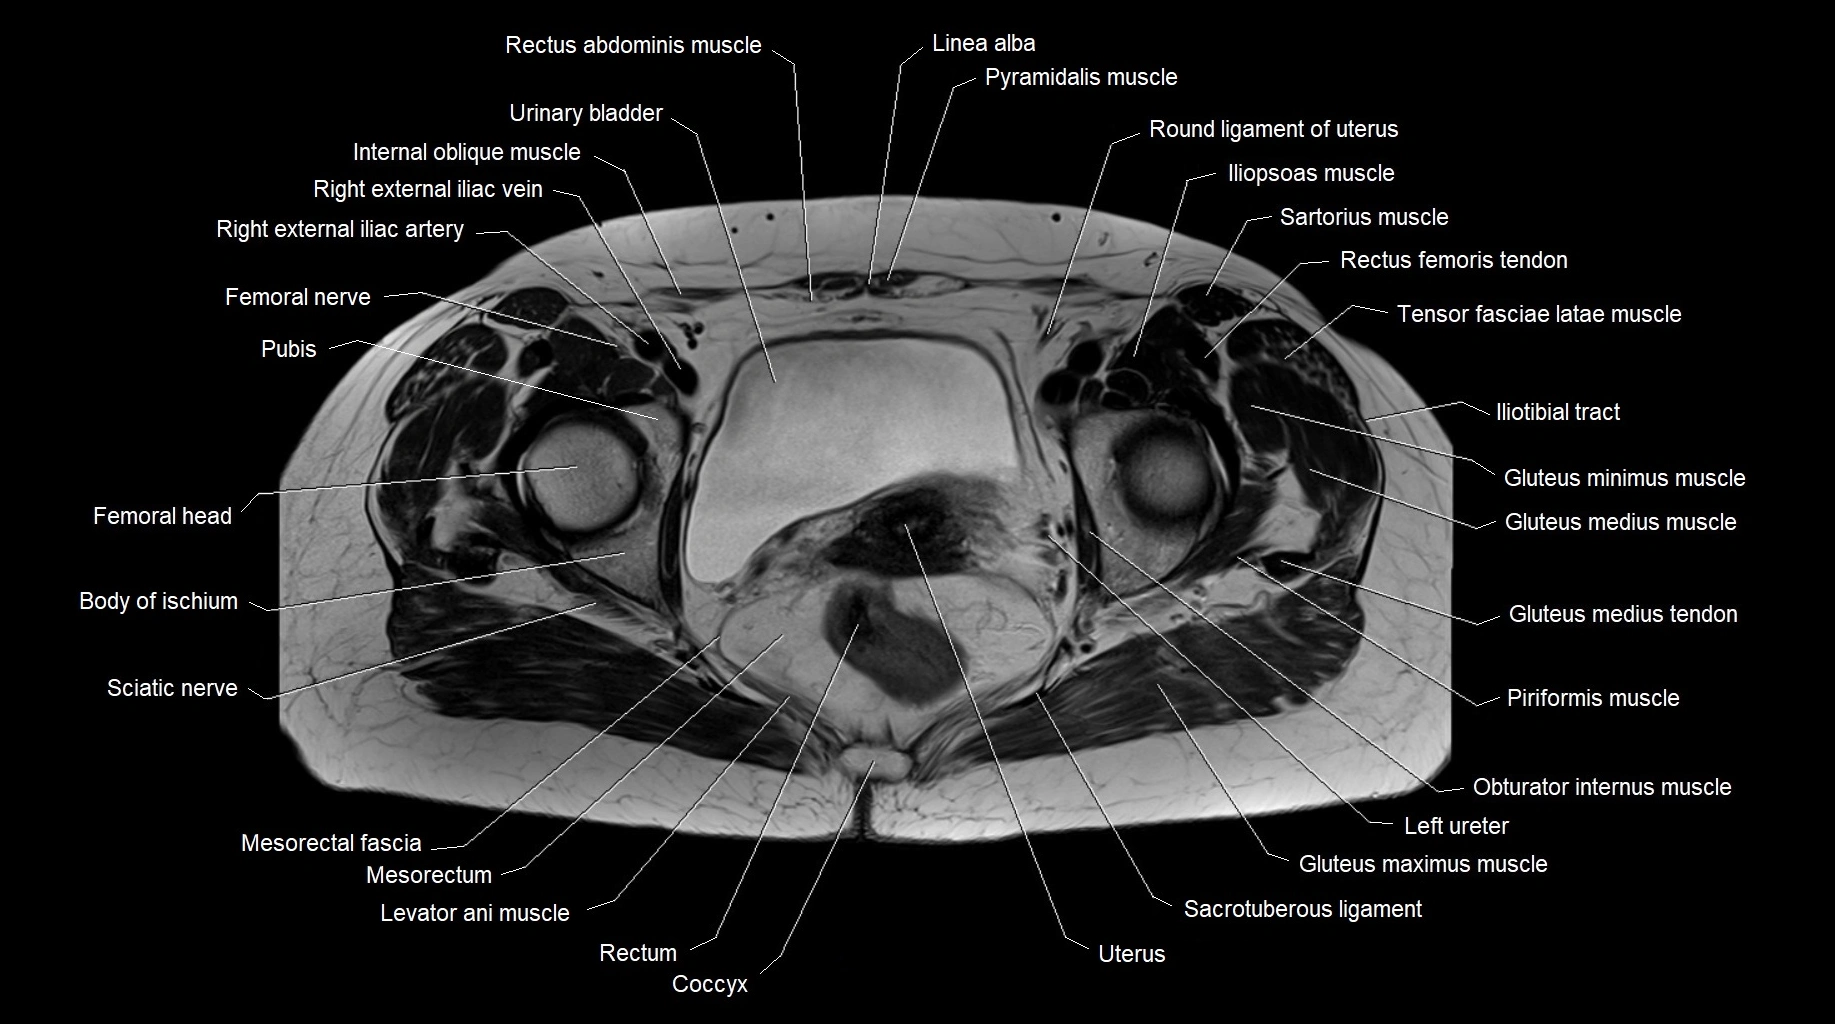

- Head of femur

- Body of ischium

- Sciatic nerve

- Piriformis muscle

- Obturator internus muscle

- Levator ani muscle

- Rectum

- Coccyx

- Sacrotuberous ligament

- Uterus

- Urinary bladder

- Round ligament of uterus

- Mesorectal fascia

- Mesorectum